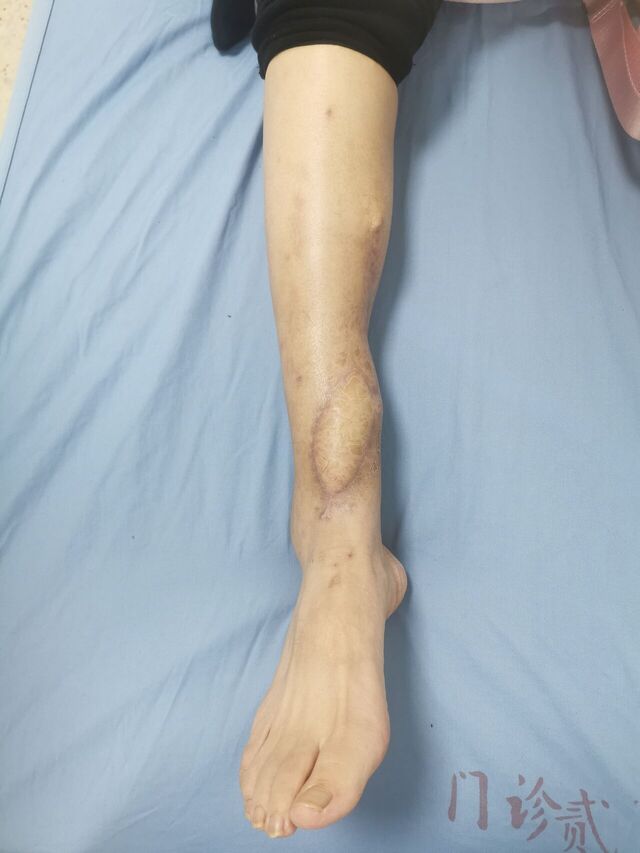

胫后动脉穿支皮瓣术后2个月